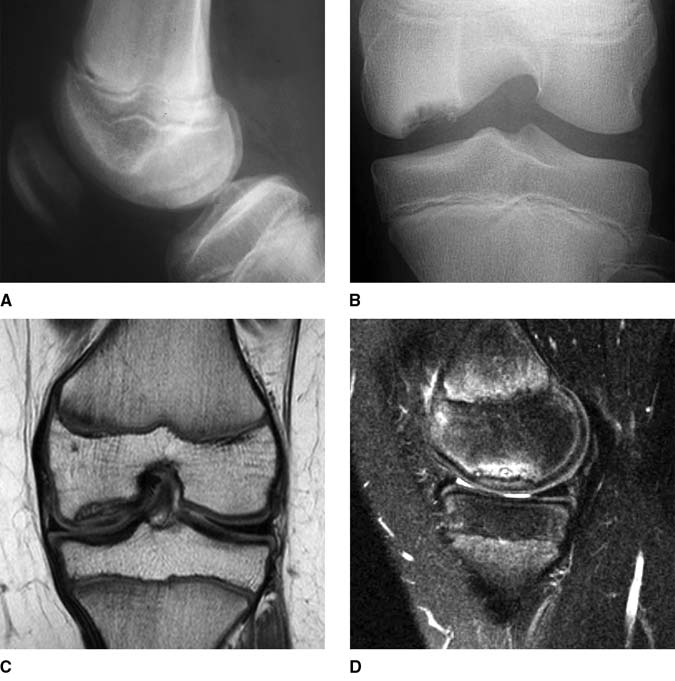

From orthopaedicprinciples.com

Osteochondritis Dissecans of the Knee Joint — Osteochondritis Dissecans Knee Brace osteochondritis dissecans is a pathologic lesion affecting articular cartilage and subchondral bone with variable clinical patterns. osteochondritis dissecans of the knee is a relatively rare condition,. symptoms of osteochondritis dissecans include pain, swelling, locking and a “giving way” sensation in the affected. osteochondritis dissecans of the knee (ocd) is a multifactorial pathology in where repetitive microtrauma. Osteochondritis Dissecans Knee Brace.